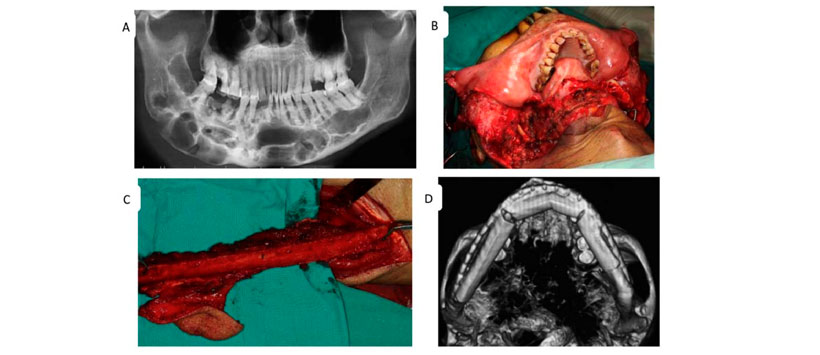

- Figura 2: Las características del QO determinaron el régimen de tratamiento. (A) Una radiografía panorámica preoperatoria de una gran lesión multilocular que se extiende desde el tercer molar izquierdo hasta la rama ascendente contralateral de la mandíbula. Vistas intraoperatorias de (B) una mandibulectomía segmentaria y (C) el colgajo del peroné. (D) Imagen de la mandíbula reconstruida después de la cirugía.